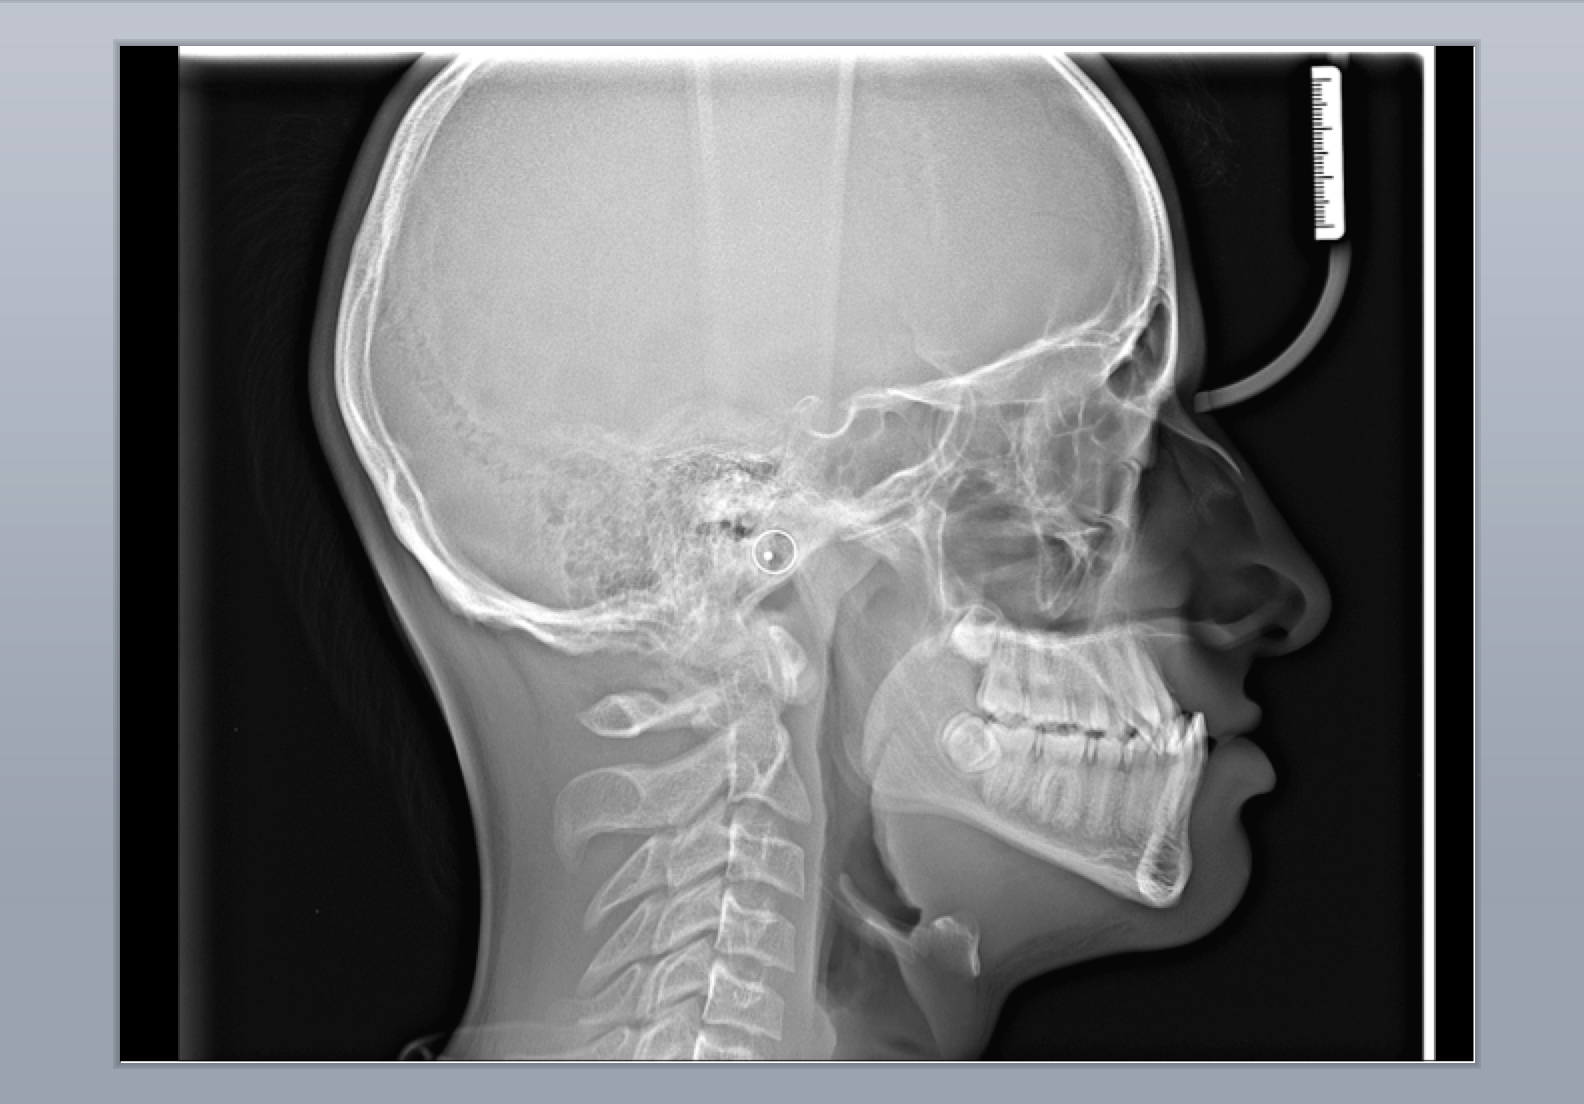

Рентгенография черепа и позвоночника: изображение и диагностика

Раздел: Необычные решения